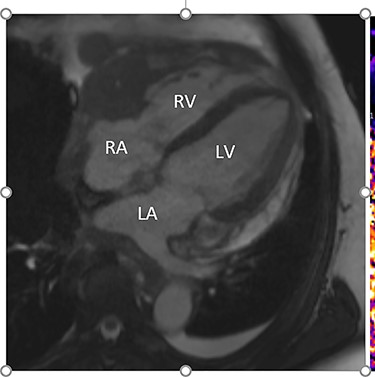

Further staging imaging was recommended by the radiology team. A CT head scan demonstrated no abnormalities, whereas CT chest–abdomen–pelvis (CAP) found significantly enlarged necrotic mediastinal lymph nodes with invasion into the pericardium and heart; bilateral adrenal nodules (suspicious for metastases) and appearances consistent with a lymphoproliferative disorder. The testicular biopsy found large lymphocytes with abundant cytoplasm and prominent nucleoli consistent with a diffuse large B-cell lymphoma (DLBCL). A positron emission tomography (PET) scan was organized at the request of the oncology team (Figs 4 and 5).

Cardiac MRI (sagittal plane) showing the lesion encasing the aorta, pulmonary artery and all coronary arteries of the heart.